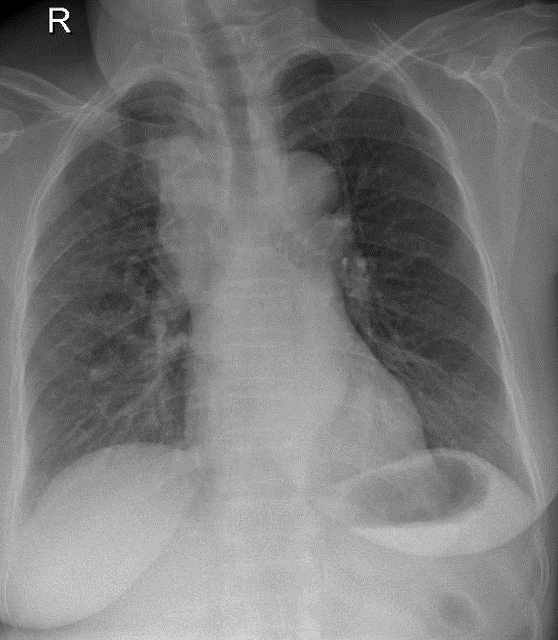

Hãy phân tích tình huống NỮ 63 tuổi -CĐ: K phổi thùy trên (P) ngang S1 (carcinoma tuyến), di căn hạch trung thất

1-Tổn thương choán chổ trung thất trước trên (P), bờ đa cung => U trung thất